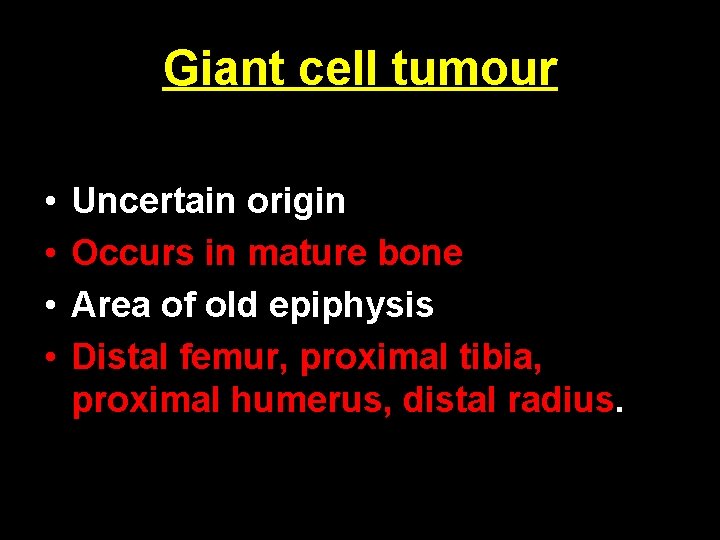

Giant cell tumour • • Uncertain origin Occurs in mature bone Area of old epiphysis Distal femur, proximal tibia, proximal humerus, distal radius.